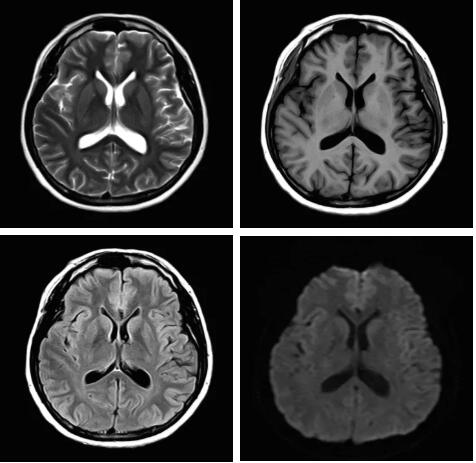

見所未見 微小腫瘤無處遁藏——

“螢火蟲”成像技術(shù) 顱內(nèi)腫瘤微小病灶檢出新發(fā)現(xiàn)

此技術(shù)主要用于神經(jīng)系統(tǒng)惡性腫瘤,以及其他腫瘤腦轉(zhuǎn)移瘤篩查。傳統(tǒng)情況下做腫瘤腦轉(zhuǎn)移篩查,很容易漏掉5mm以下小病灶,臨床發(fā)現(xiàn)后干預(yù)治療比較晚,要實(shí)現(xiàn)2mm高空間分辨率和超薄層全腦掃描在保證信噪比的情況下需要很長時(shí)間大概十多分鐘,而且薄層增強(qiáng)序列顱內(nèi)血管呈高亮信號,會(huì)干擾顱內(nèi)小病灶的觀察,血管和小病灶區(qū)分困難。佳能”螢火蟲”成像技術(shù)既可以實(shí)現(xiàn)高空間分辨率和超薄層(最薄可實(shí)現(xiàn)0.2mm)全腦掃描,掃描時(shí)間短,2-3分鐘即可實(shí)現(xiàn)全腦3D掃描,同時(shí)避免了血管高亮信號的干擾,對顱內(nèi)原發(fā)或繼發(fā)的微小腫瘤檢查有重大意義。“螢火蟲”成像技術(shù)具有磁敏感效應(yīng),對于亞急性血敏感敏感,可以區(qū)分出血和強(qiáng)化的腫瘤。